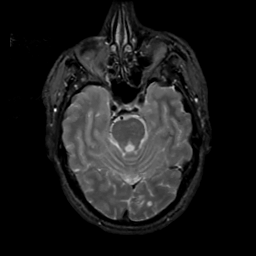

MR Study #6, March 17, 1991 -- Slice #16

[Home][Help][Clinical][Tour 1][Tour 2] Slice 16